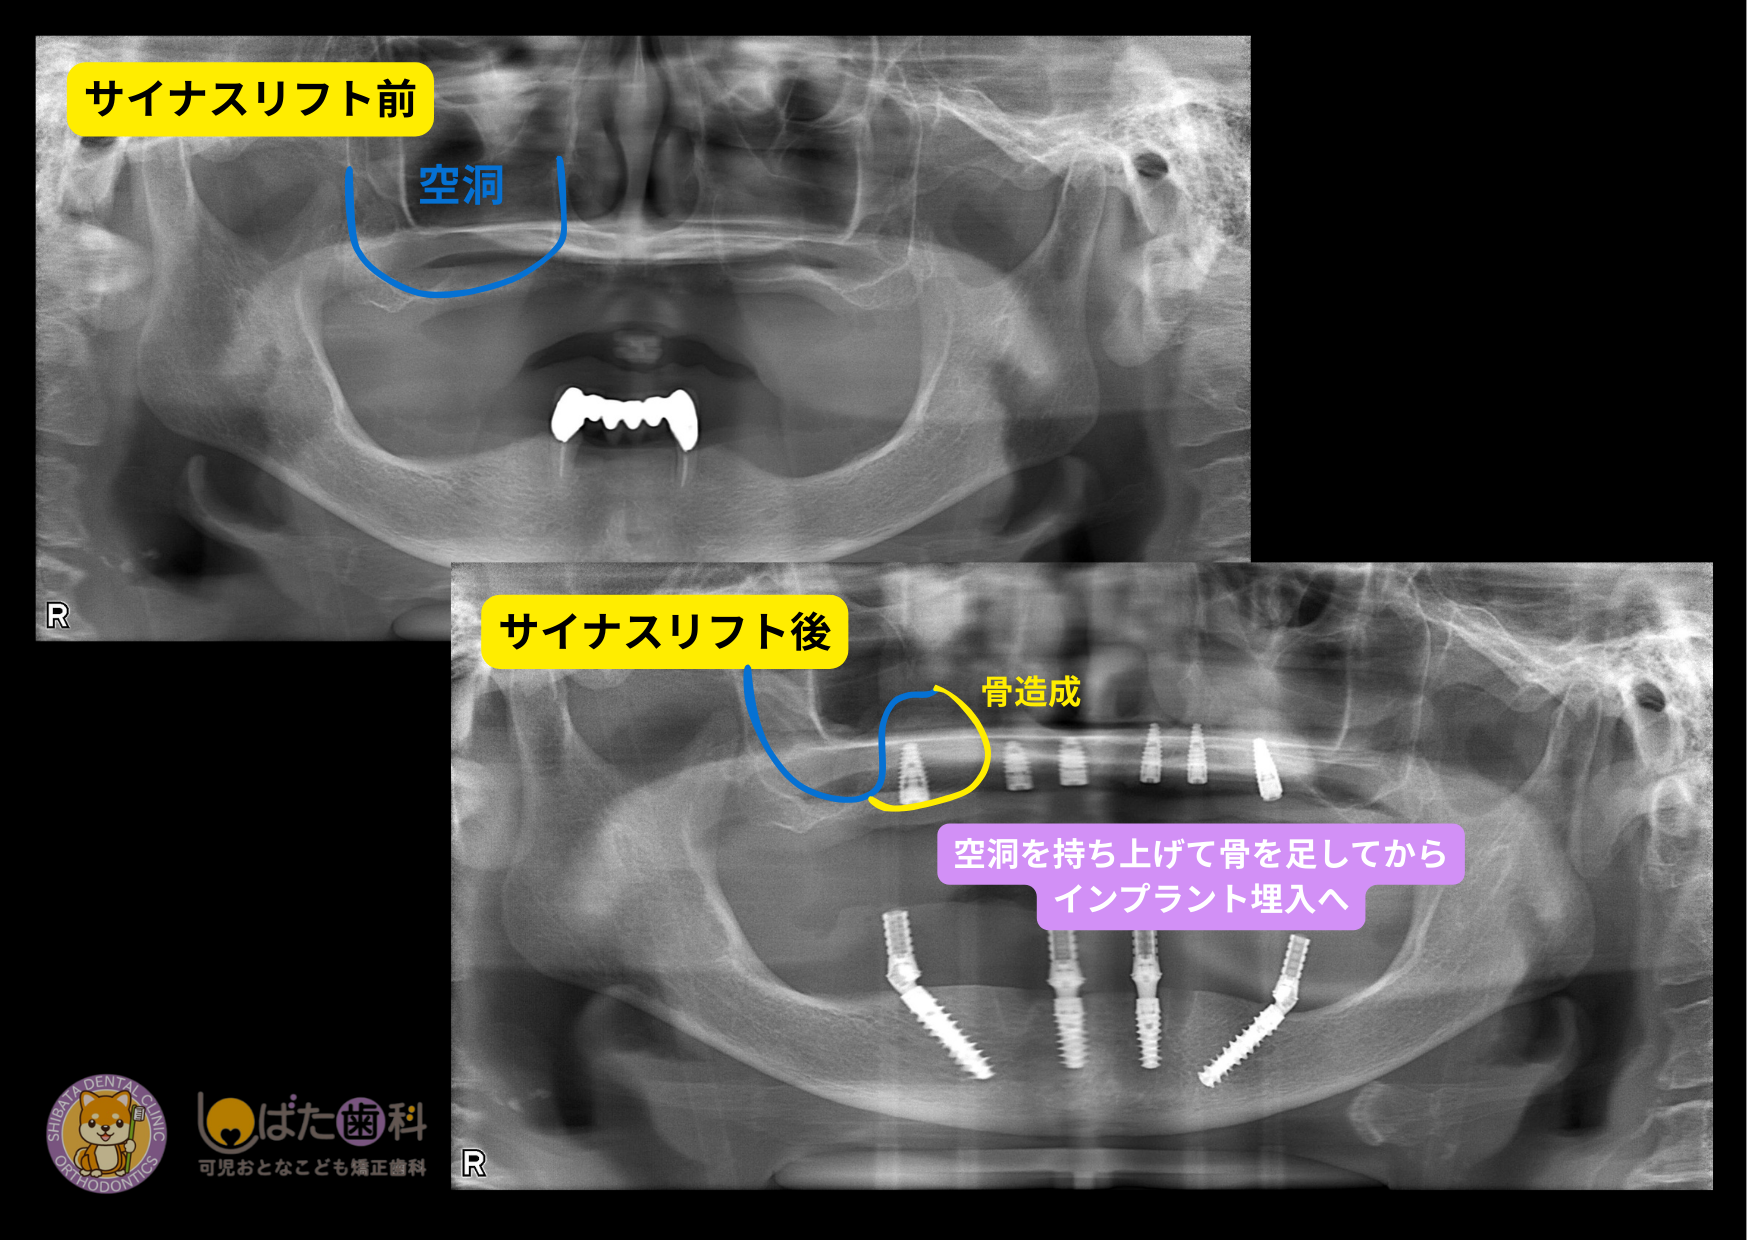

「骨が3mmしかない」といった重度の骨不足の方に選ばれるのがサイナスリフトという術式です。他院で断られた方の多くは、この術式が必要なケースです。

3-1 サイナスリフトの仕組み

サイナスリフトは歯茎の横側からアプローチし、上顎洞の粘膜を直接目で確認しながら、専用の器具を用いて慎重に持ち上げていく方法です。粘膜を破らないように細心の注意を払いながら操作し、持ち上げたスペースに骨補填材を入れることで、インプラントを支えるための骨を作ります。ソケットリフトと比べてより広い範囲のスペースを確保できるため、骨の不足が大きい場合でも対応でき、1度の処置で十分な骨の量を作ることが可能です。上顎の骨が大きく失われている方にとって、安全性と確実性を重視した方法といえます。

CTで精密検査を行った結果、上顎の骨の厚みが不足している状態でした。そこでまず行ったのがサイナスリフトです。

①サイナスリフトを実施

上顎洞の粘膜を持ち上げ、骨補填材を填入

②サイナスして骨ができるまで待機

骨は一瞬でできるもではありません。しっかりと安心した骨になるまで待つことが重要になります。

この患者さんはサイナスリフト手術後、約6ヶ月の待機期間を設けました。

この待機期間は「何もしていない時間」ではありません。骨がしっかり成熟することで、将来のインプラントの長期安定に繋がります。

③6ヶ月後に埋入オペ

CTで骨造成が十分確認できた段階で、インプラント埋入オペを実施しました。

サイナスリフトでしっかり骨ができていたため、安定した初期固定が得られ 予定通り埋入を完了することができました。